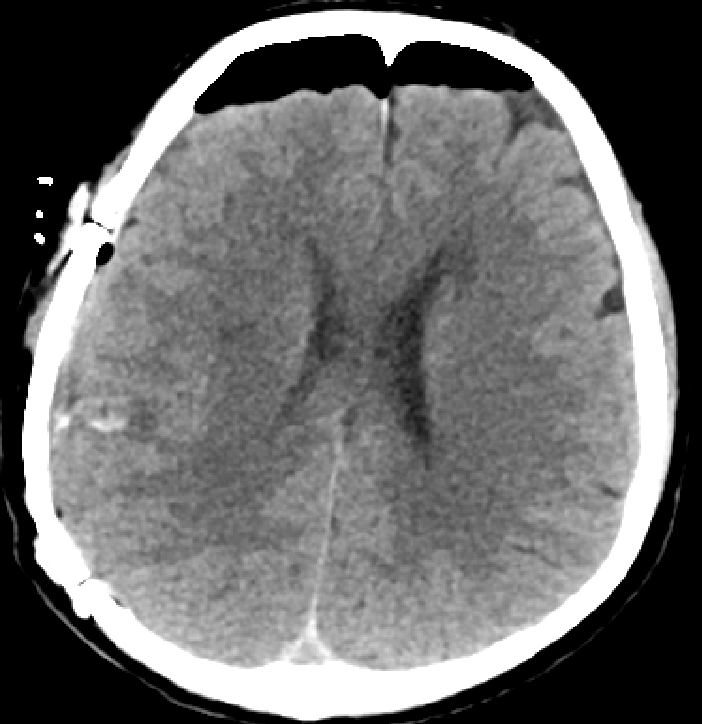

影像复查显示脑内血肿基本消失

术后第2天,王大叔意识恢复;第5天可自主进食;经过一段时间的康复训练,他已能在助行器辅助下行走。“要不是医院救得快,我这条命可能就没了。”王大叔握着医护人员的手感慨道。